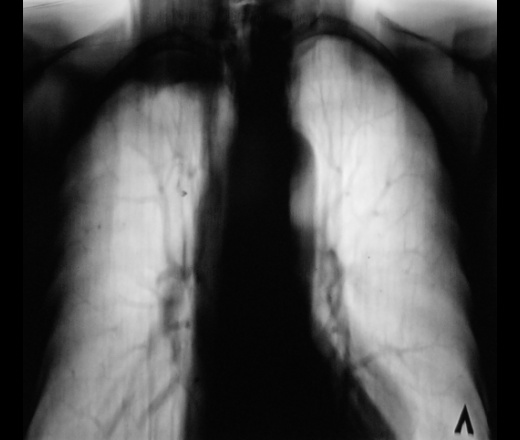

Пол пациента: Мужской пол Тип патологии: Другое Область исследования: Грудная клетка и верхние дыхательные пути Методы исследования: Rg Контроль после флюорографии. Верхушка вызвала недоверие https://radiomed.ru/sites/default/files/styles/case_slider_image/public/user/12/6.dscn0396.jpg?itok=dcnuKHCZ https://radiomed.ru/sites/default/files/styles/case_slider_image/public/user/12/7.dscn0396a.jpg?itok=wfK2iVjR ID:23836 Sun, 21/10/2012 - 12:17 #1 maker4ik Offline Last seen: 8 years 9 months ago Joined: 19.10.2011 - 17:49 Posts: 2682 Панкост? Sun, 21/10/2012 - 19:46 #2 И.Бондаренко Offline Last seen: 14 hours 57 min ago Joined: 13.09.2011 - 22:55 Posts: 9208 Возраст пациента? Sun, 21/10/2012 - 22:23 #3 Катенёв Валенти... Offline Last seen: 7 years 3 months ago Joined: 22.03.2008 - 22:15 Posts: 54876 В районе 50 лет. Mon, 22/10/2012 - 09:13 #4 Андрей Багаев Offline Last seen: 11 years 4 months ago Joined: 28.01.2011 - 19:14 Posts: 57 а 1 ребро целое? Mon, 22/10/2012 - 22:48 #5 И.Бондаренко Offline Last seen: 14 hours 57 min ago Joined: 13.09.2011 - 22:55 Posts: 9208 За периферический Tue, 23/10/2012 - 00:50 #6 Петрович Offline Last seen: 7 years 5 months ago Joined: 22.03.2009 - 01:13 Posts: 3908 Скорее воспалительная инфильтрация с мощной плевральной реакцией. Архив есть? Неоднозначно всё

Панкост?

а 1 ребро целое?

За периферический

Скорее воспалительная инфильтрация с мощной плевральной реакцией.